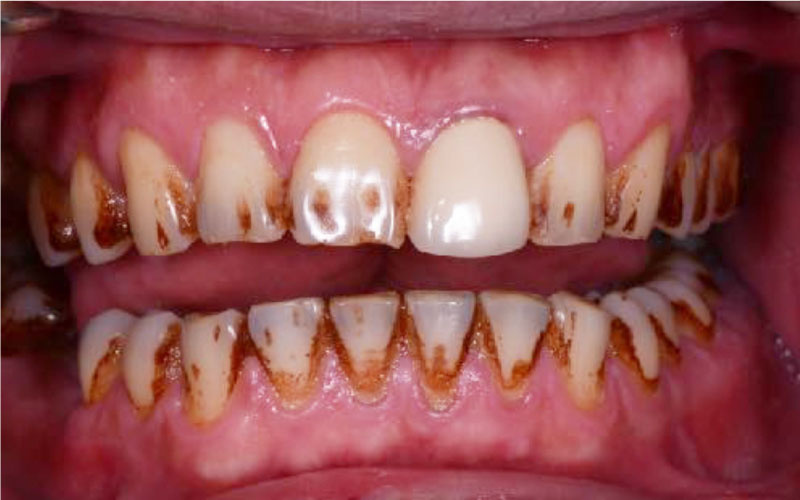

Before

• 牙齒染色

• 茶垢、菸垢附著

After

• 全口噴砂